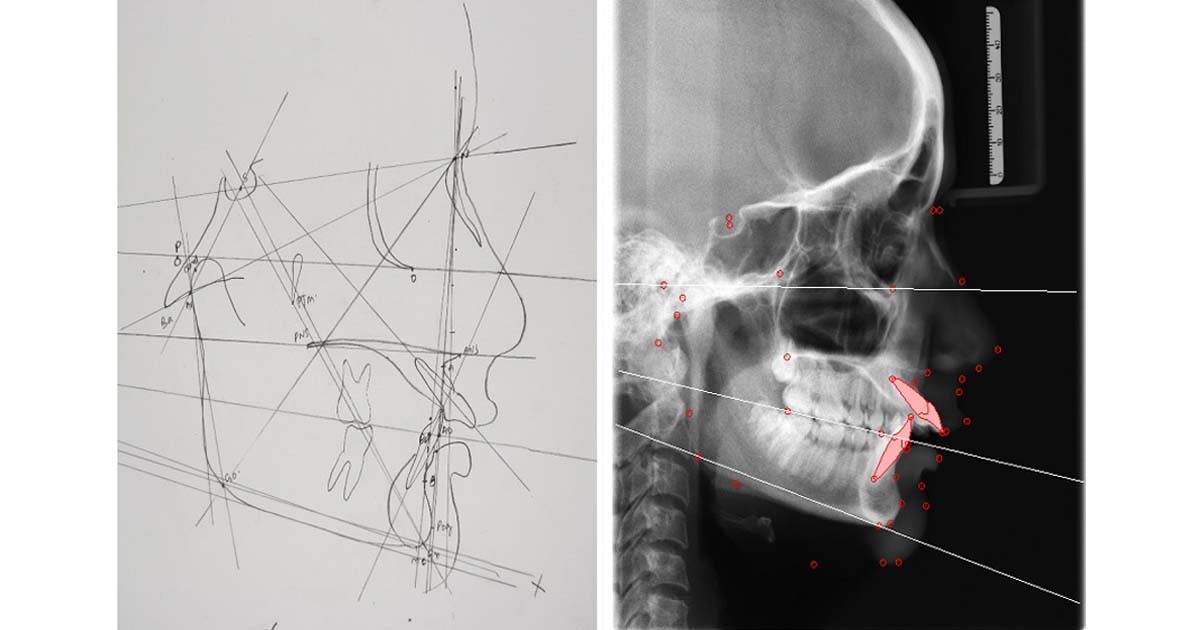

Cephalometric tracing by hand:

Not only is the manual tracing of cephalographs time-consuming, but it is also error-prone, as different persons interpret different points with varying degrees of precision due to inter-observer variability. The tracings are also done on delicate and thin sheets, which are often difficult to store and tear very easily.

New Software for Cephalometric Tracing

This new technology is not given enough importance, but cephalometric tracing of digital radiographs and photographs through software is one of the major advancements in orthodontic treatment. It helps assess a patient’s growth during orthodontic procedures. Not only does it save time and storage space, as compared to manual tracing on cephalometric films, but it also improves analysis accuracy by providing precise soft and hard tissue markings. There are minimal chances of inter-observer variability, ensuring consistent and accurate results with every cephalometric analysis.